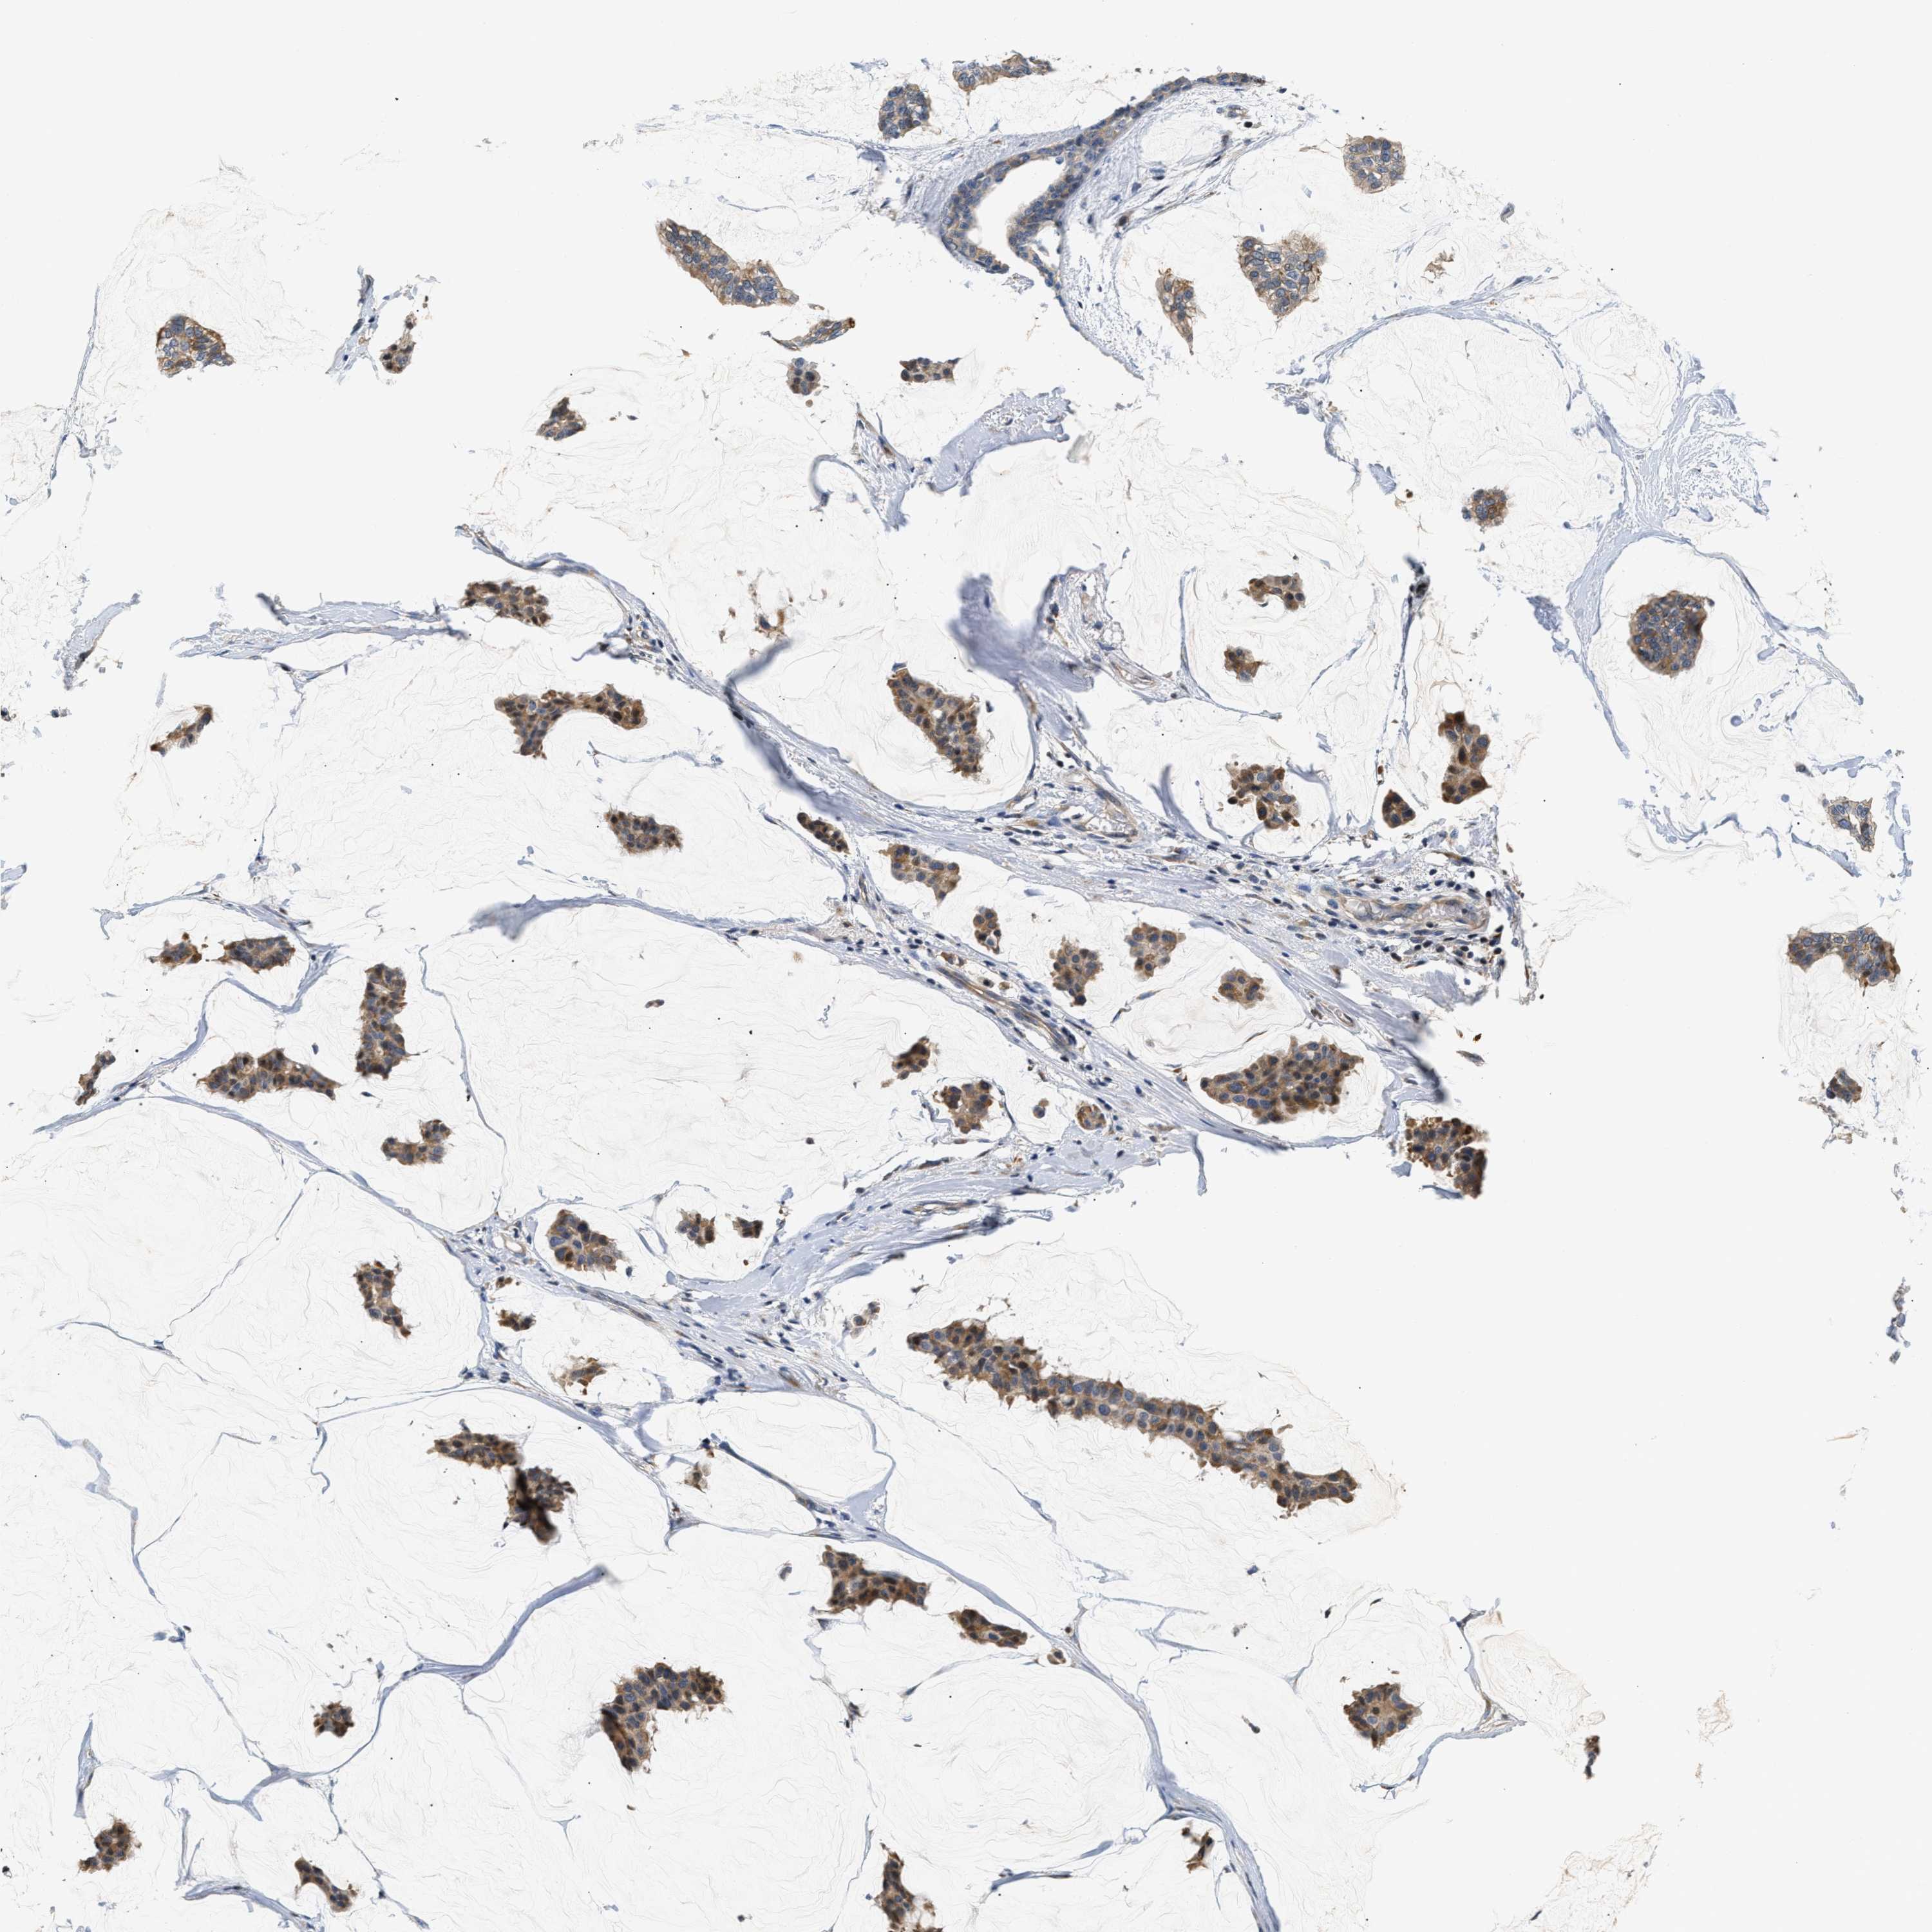

CANCER BREAST CANCER Show tissue menu

BRCA TCGA BRCA VALIDATION PROTEIN EXPRESSION